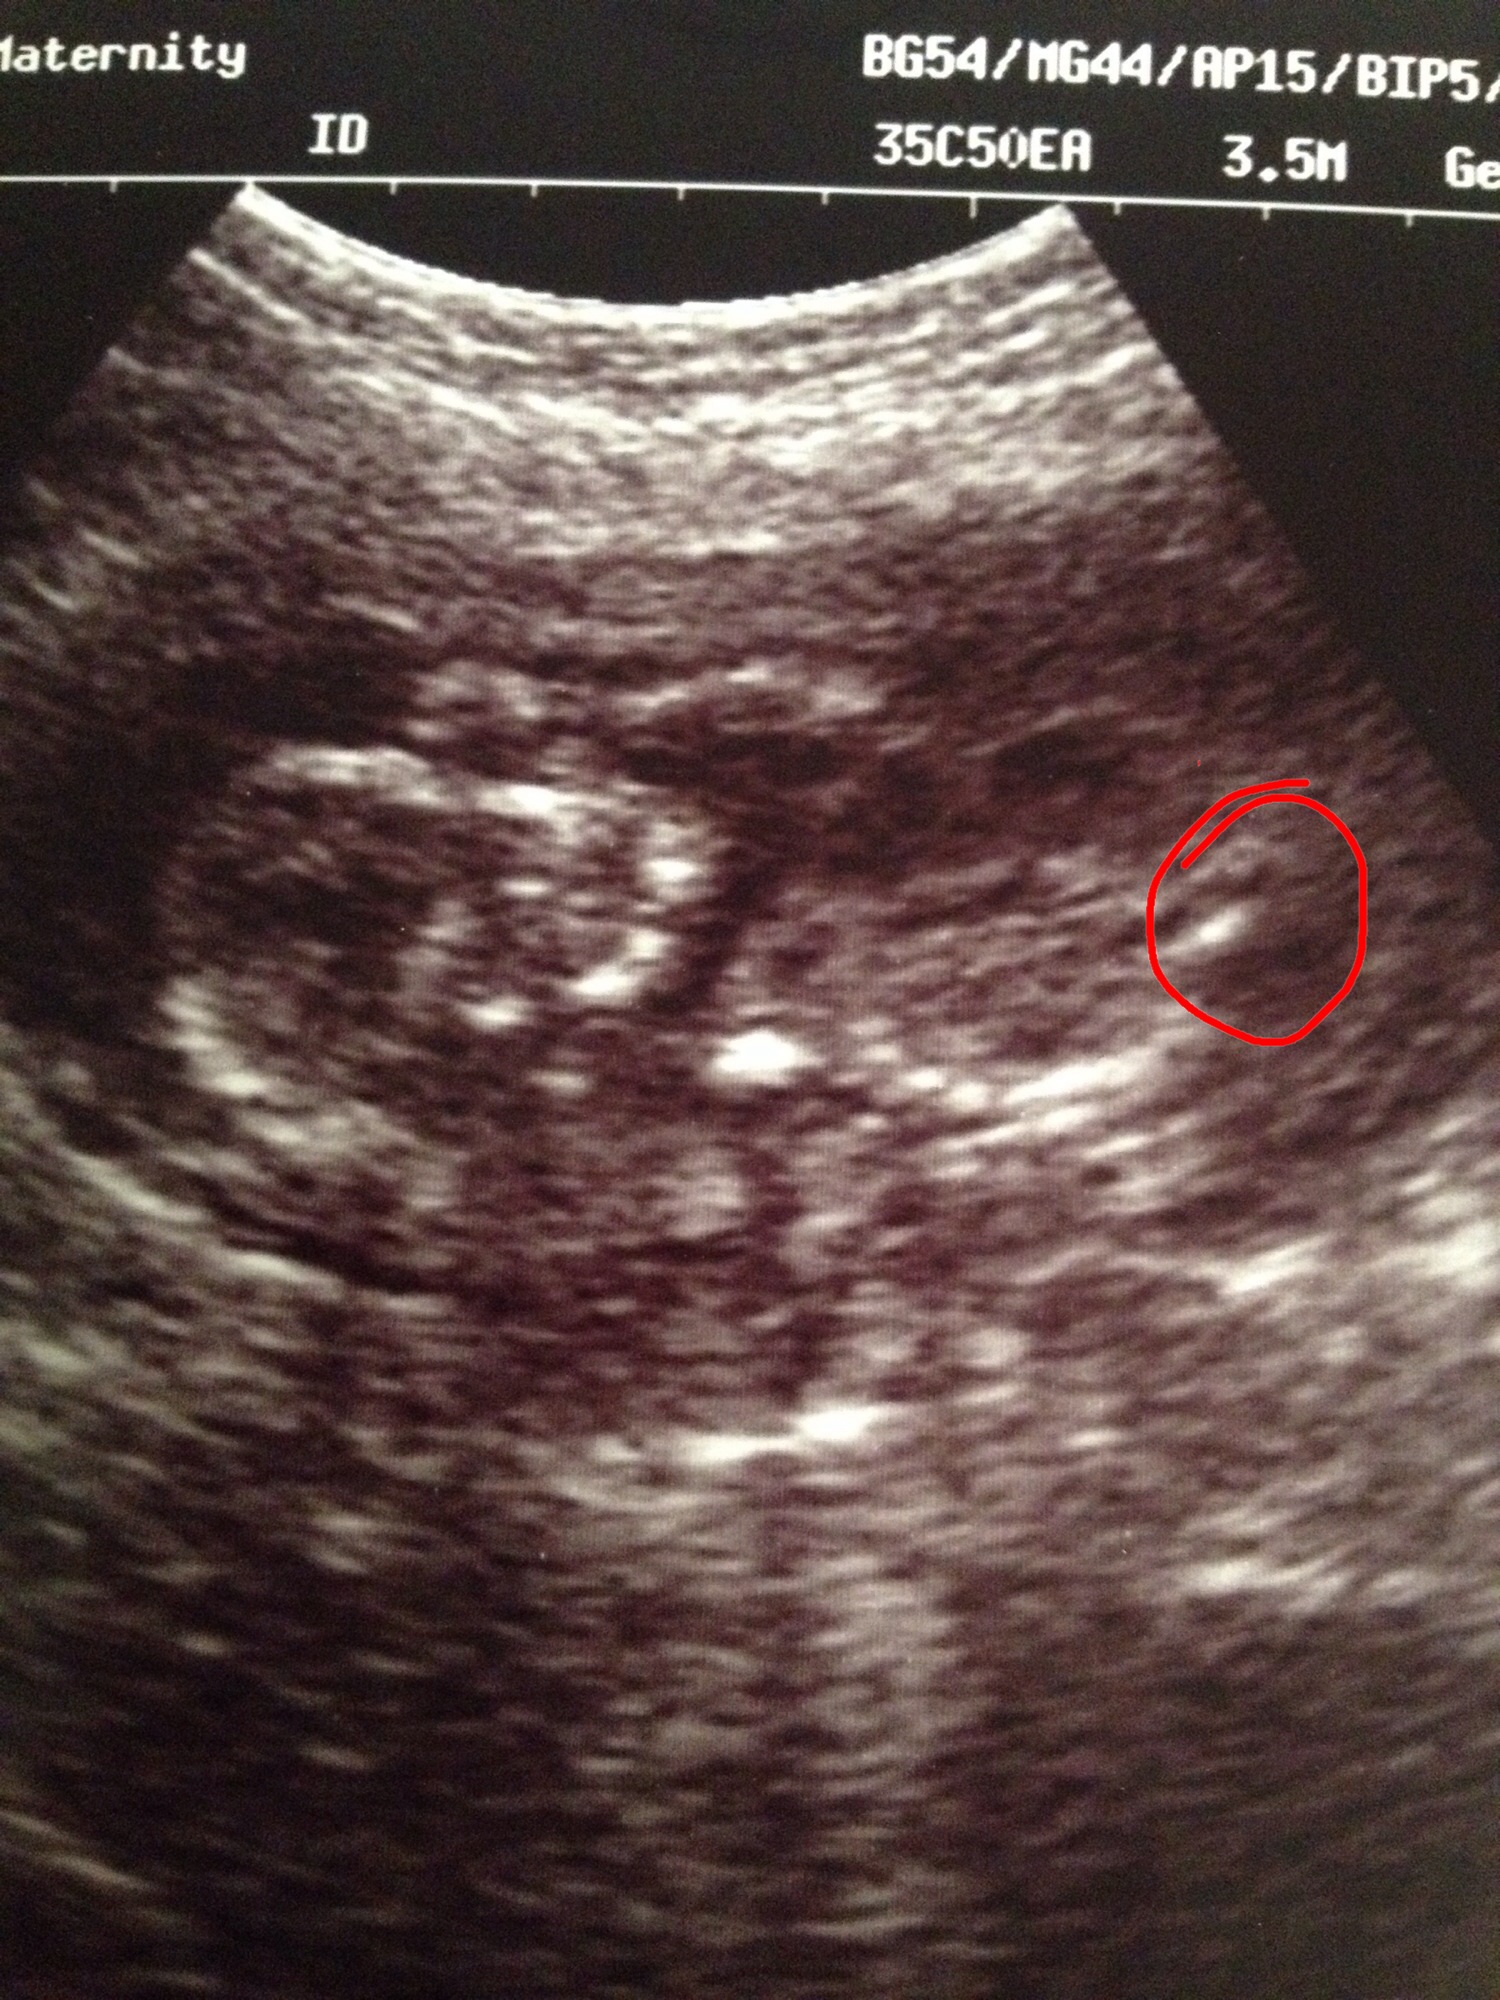

I'm pretty sure there's no gender clues in these pics as they are such awful quality but I decided to see your opinions. These are 14 weeksAttachment 19537 babys head is on the left with hand up by the face and the body to the right. Attachment 19538 this ones even harder to make out. Babys head to the left and body to the right. Attachment 19539 and a shot of the bottom and legs